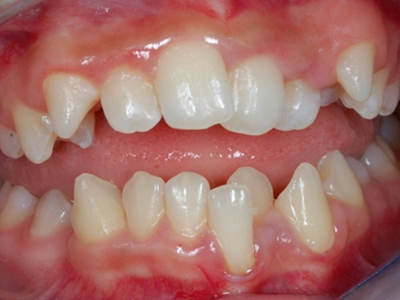

阻生牙是指由于邻牙、骨或软组织的阻碍而只能部分萌出或完全不能萌出,且以后也不能萌出的牙。引起牙阻生的成因,主要是由于颌骨缺乏足够的空间容纳全部恒牙。常见的阻生牙为下颌第三磨牙、上颌第三磨牙及上颌尖牙。

阻生牙主要原因是随着人类的进化,颌骨的退化与牙量的退化不一致,导致骨量相对小于牙量,颌骨缺乏足够的空间容纳全部恒牙。

发育正常的牙齿同时正畸治疗又不需要进行拔牙矫治,通常需要对阻生牙进行牵引治疗,引导进入牙弓,而对于发育异常的阻生牙加之正畸治疗需要进行拔牙矫治,通常可以考虑将阻生牙拔除,而避免再拔发育正常的前磨牙,即降低了正畸治疗的难度及不确定性,又保留了相对正常的牙齿。